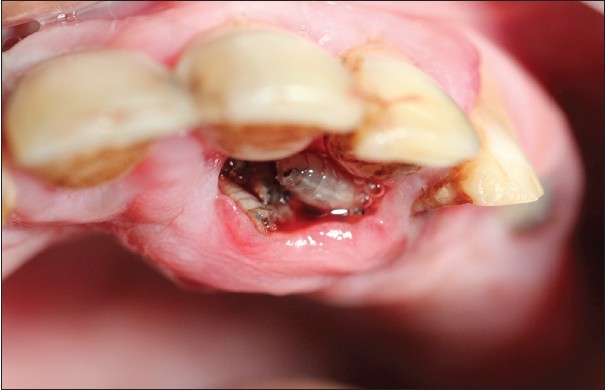

So, Oral Myiasis is a rare disease caused by the Larvae of dipterans. It is reported mostly in developing countries. Myiasis can occur in various parts of our body, not only in the oral region. It can be in the skin, nose, ear, eyes.

However, the treatment is the surgical removal of larvae. And the result of the activities of larvae is treated after its removal. Turpentine solution help in the extraction of maggots.